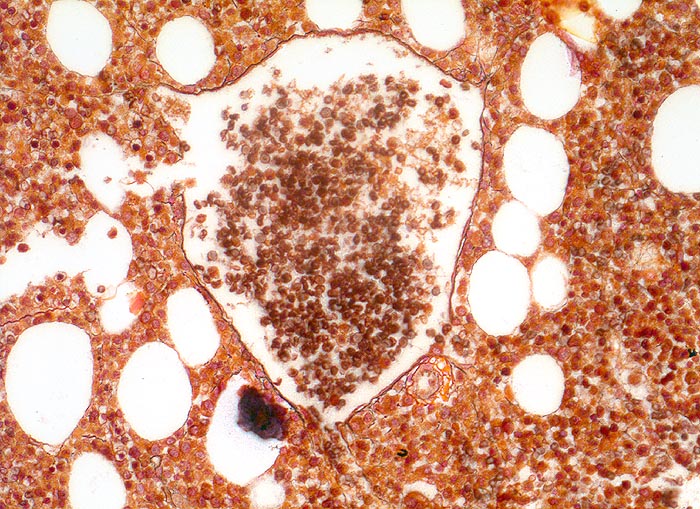

PathoPic ID 4027 - normales blutbildendes Knochenmark

normales blutbildendes Knochenmark

Knochenmark, Beckenkamm

Im normalen Knochenmark sind sehr wenig Retikulinfasern nachweisbar. Diese sind vor allem um die Sinusoide nachweisbar.

200